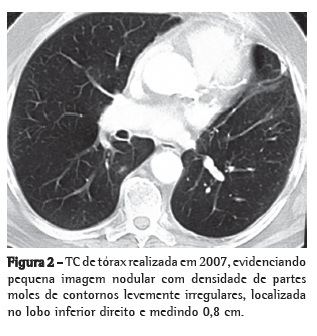

Paciente masculino de 71 anos de idade, com antecedente de lobectomia superior esquerda com ressecção do pericárdio por invasão local e linfadenectomia mediastinal há cinco anos (Figura 1). Estadiamento patológico IIB (T3N0M0). No seguimento com exame de imagem, achado de lesão pulmonar contralateral-0,8 cm no segmento superior do lobo inferior direito-não presente nos controles anteriores (Figura 2).